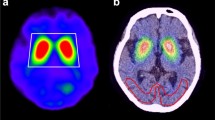

Measurement of striatal accumulation ratio and asymmetry

Automated Anatomical Labeling Volumes-of-Interest. Extracted volumes-of-interest (VOI) for the caudate nucleus (Caudate) and putamen (Putamen) were obtained from the "Automated Anatomical Labeling (AAL1) atlas." Regions-of-interest for the occipital lobe were extracted from the regions Occipital_Inf, Occipital_Mid, Occipital_Sup, Lingual, Cuneus, and Calcarine. The combined regions were used as the region-of-interest for the occipital lobe. The VOI was created, displaying the caudate nucleus in red, the putamen in green, and the occipital lobe in blue